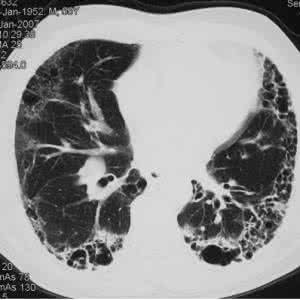

肺间质纤维化是由多种原因引起的肺间质的炎症性疾病,病变主要累及肺间质,也可累及肺泡上皮细胞及肺血管。病因有的明确,有的未明。明确的病因有吸人无机粉尘如石棉、煤;有机粉尘如霉草尘、棉尘;气体如烟尘、二氧化硫等;病毒、细菌、真菌、寄生虫感染;药物影响及放射性损伤。本病属中医“咳嗽”、“喘证”、“肺瘘”等范畴。

弥慢性肺间质纤维化是由多种原因引起的肺间质的炎症性疾病,病变主要累及肺间质,也可累及肺泡上皮细胞及肺血管。病因有的明确,有的未明。

约15%的IPF病例呈急性经过,常因上呼吸道感染就诊而发现,进行性呼吸困难加重,多于6个月内死于呼吸循环衰竭。绝大数IPF为慢性型(可能尚有介于中间的亚急性型),虽称慢性,平均生存时间也只有3.2年。慢性型似乎并非急性型演变而来,确切关系尚不了解。